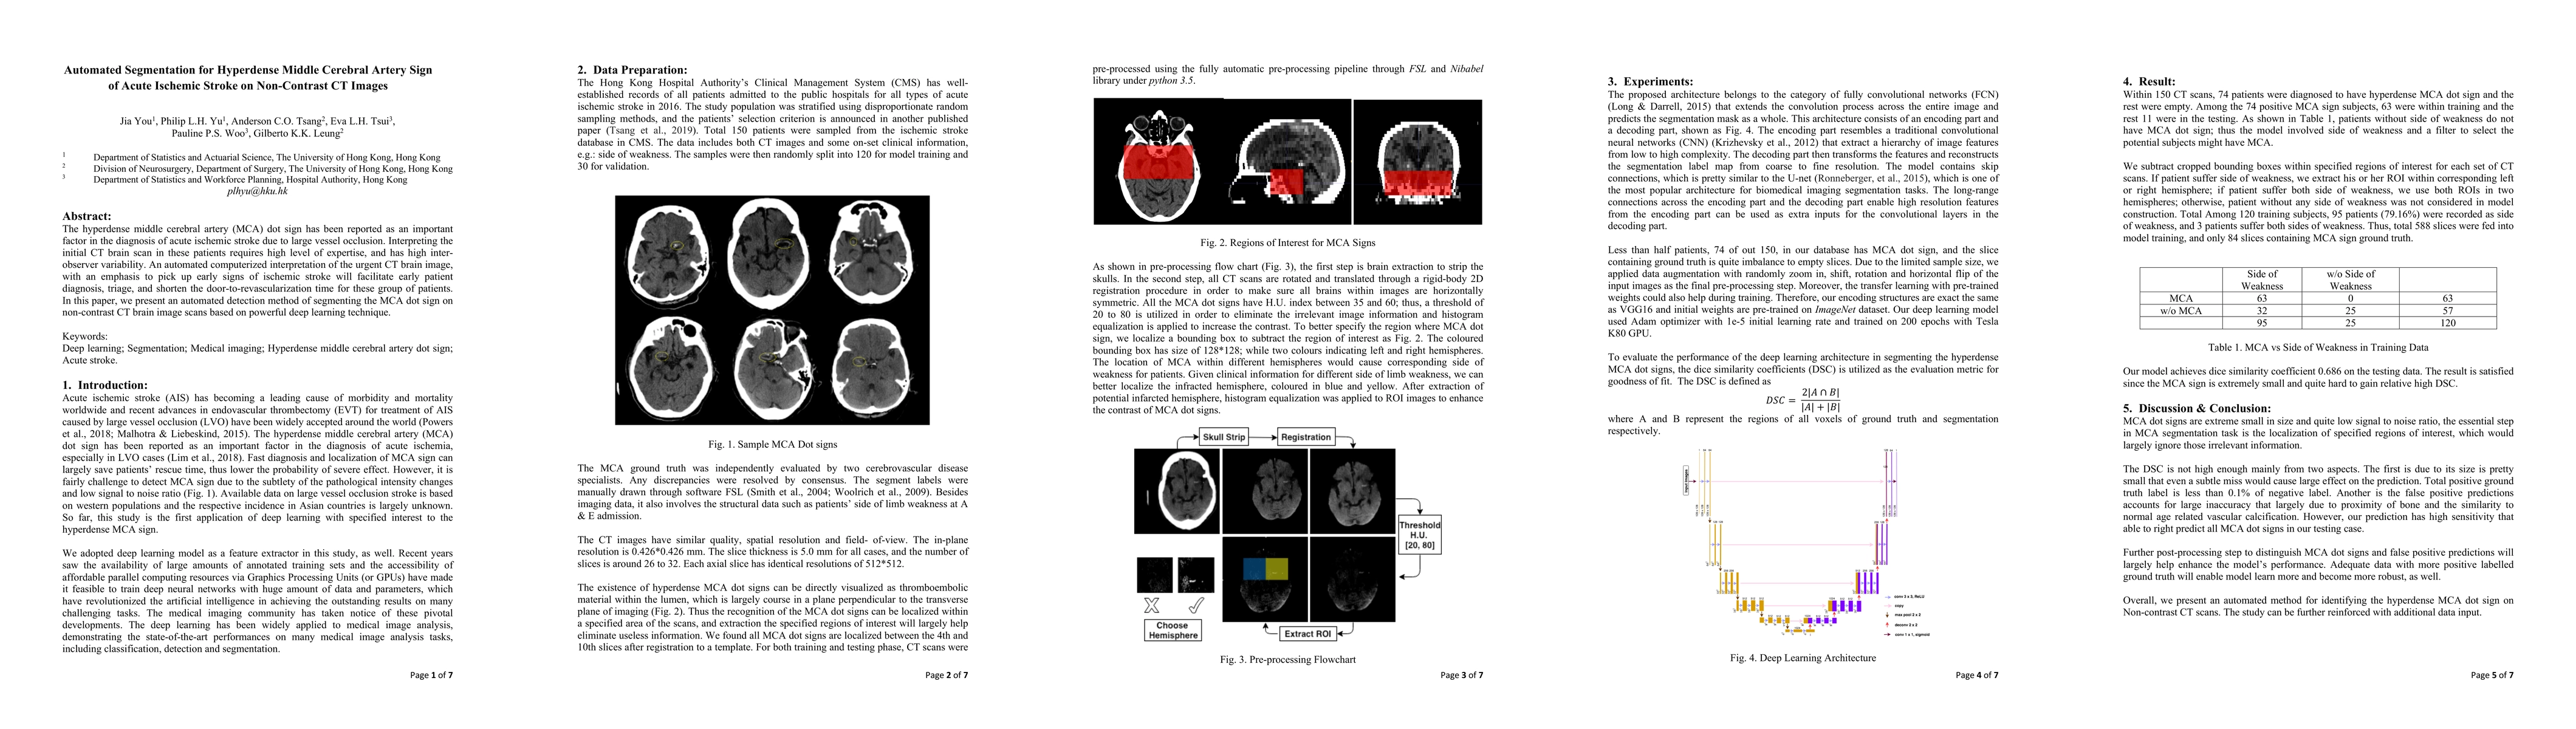

The hyperdense middle cerebral artery (MCA) dot sign has been reported as an important factor in the diagnosis of acute ischemic stroke due to large vessel occlusion. Interpreting the initial CT brain scan in these patients requires high level of expertise, and has high inter-observer variability. An automated computerized interpretation of the urgent CT brain image, with an emphasis to pick up early signs of ischemic stroke will facilitate early patient diagnosis, triage, and shorten the door-to-revascularization time for these group of patients. In this paper, we present an automated detection method of segmenting the MCA dot sign on non-contrast CT brain image scans based on powerful deep learning technique.